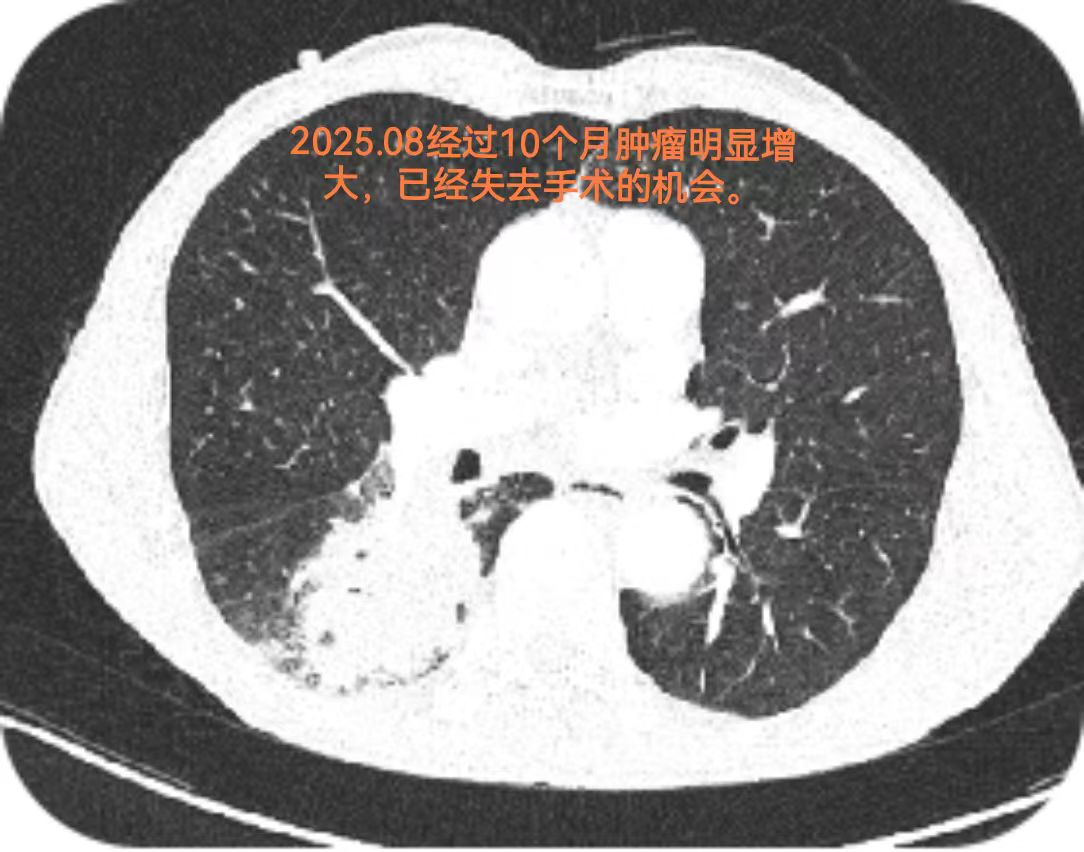

2025年8月,因反复咳嗽、肺部感染,吴伯来到我院就诊。胸部CT提示右下肺占位性病变,病理活检最终确诊为右下肺鳞状细胞癌,临床分期cT3N1M0(ⅢA期)。

很多人可能不清楚这个分期的意义:ⅢA期肺鳞癌属于局部晚期,肿瘤侵犯范围较广且伴随淋巴结转移,直接手术切除难度极大——不仅难以彻底清除病灶,还可能因手术创伤严重影响患者后续生活质量;而单纯内科治疗效果又存在局限,患者的治疗与康复之路面临诸多挑战。

更让人惋惜的是,早在2024年10月,吴伯就已发现肺部异常,却因未积极治疗导致病情加重。这也再次提醒大家:肺部不适及时就医、发现异常尽早干预,对癌症诊疗至关重要。